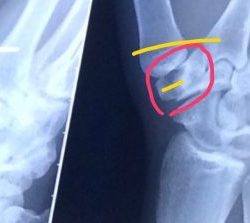

大阪桐蔭の優勝から一夜明け小僧は緊急入院に大会二回戦の試合中に右手大菱形骨を骨折し大会中は離脱したくないとテーピングでぐるぐる巻きに そして今手術中 イメージ写真折れた大菱形骨と開いた親指を戻す為に二箇所をビスで固定するみたいですなんかレアな骨折らしい